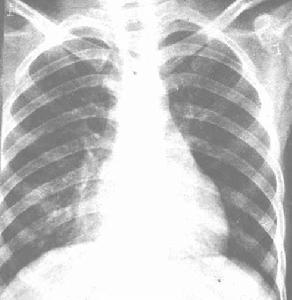

其他輔助檢查:X 線胸片表現為結節性肺基底部緻密灶,為敗血症血行播散所致。按肺段分布的片狀陰影表示為吸入性感染所致。廣泛的模糊病灶表示有化膿性血栓形成。